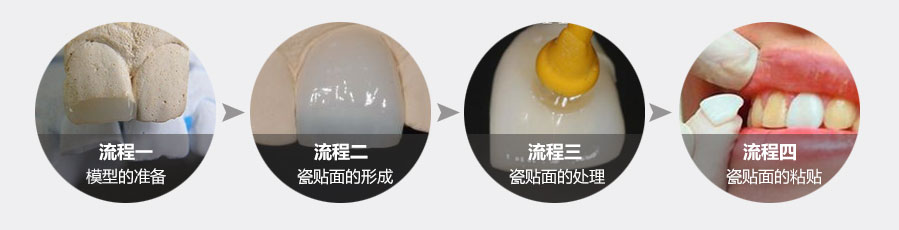

牙贴面是指在不磨牙或少磨牙的情况下,应用粘接材料,将薄层瓷修复体固定于患牙唇、颊面,以恢复影响好看的缺损、遮盖变色等缺陷的一种修复方法。

使用于中、重度四环素牙、小面积崩裂、牙缝隙